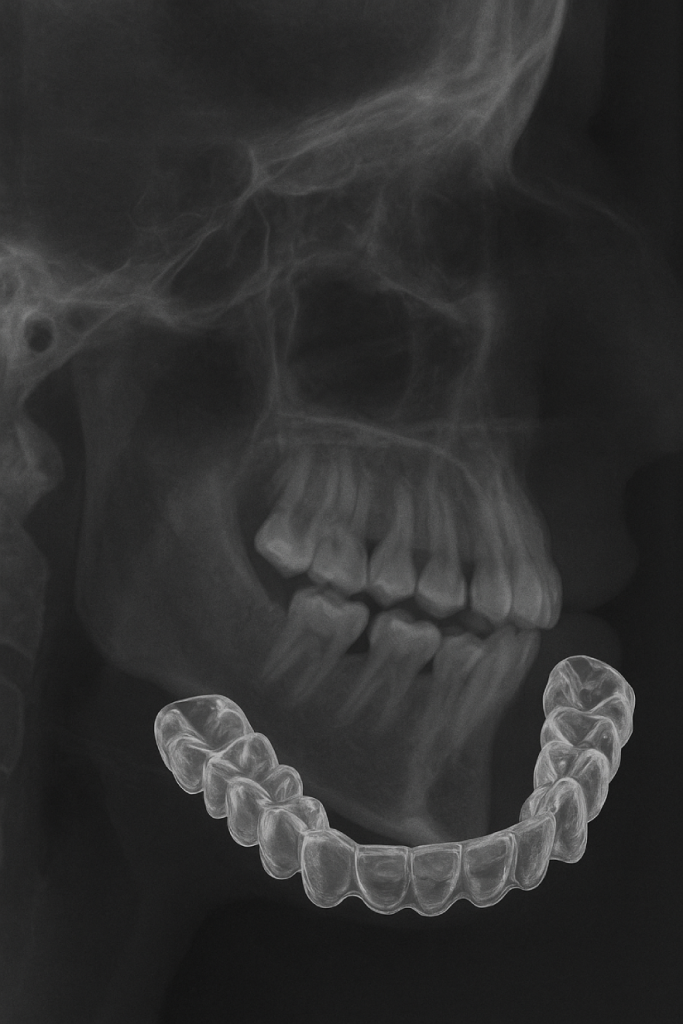

CBCT y alineadores dentales: la clave para una ortodoncia invisible precisa y segura

La ortodoncia invisible con alineadores ha revolucionado la manera de corregir la posición dental. Sin embargo, para lograr resultados predecibles y seguros, la planificación radiológica en 3D mediante CBCT (Cone Beam Computed Tomography) se ha convertido en una herramienta indispensable tanto para el ortodoncista como para el paciente.

Mientras que las radiografías tradicionales muestran solo una vista bidimensional, el CBCT proporciona una imagen tridimensional completa del hueso, raíces y estructuras anatómicas.